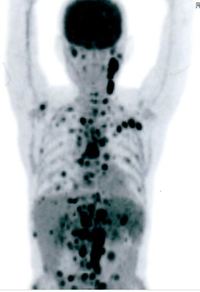

PET CT showed multiple hypermetabolic marrow lesions seen involving the axial skeleton. Multiple hypermetabolic left cervical bilateral left cervical and bilateral subpectoral and mediastinal nodes were also noted. On clinical suspicion of lymphoma bone marrow aspirate was reported elsewhere with maroow plasmacytosis of 15% and bone marrow  biopsy was done and sent.